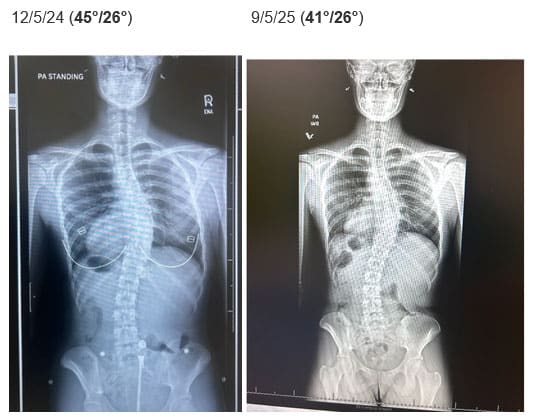

• Relevant Medical History: Diagnosed with Adolescent Idiopathic Scoliosis (AIS) at age 15, where her curve was measured at 45° in the thoracic spine and 26° in the lumbar spine. Bracing was not recommended due to growth plates being mostly closed.

• Radiographic Changes: After 6 months of consistent practice, a follow-up X-ray showed an improvement in her spinal curves:

• Her thoracic curve reduced from 45 degrees to 41 degrees (taking her out of surgical range).

• Her lumbar curve stayed at 26 degrees.

• Another 6 month scan was taken after these improvements, which showed the Cobb angles stable at 41/26 degrees respectively.